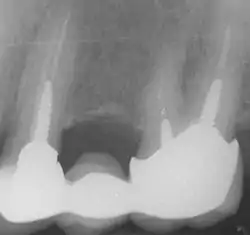

In the picture at right, the two teeth on the extreme left and right are the ones under discussion. The two teeth in the middle have been endodontically treated, but do not have post and cores.